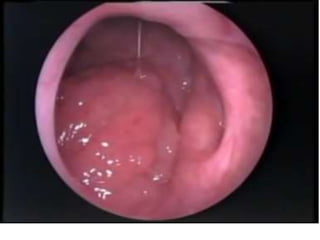

Oro-Pharynx  Situated behindoral cavity  Extend from the level of the soft palate to the level of the hyoid bone.  Superiorly- communicates to the nasopharynx through the pharyngeal isthmus.  Anteriorly- It communicates with the oral cavity  Posteriorly- opposite to C2 and C3.  Lateral wall- Palatine tonsils and anterior & posterior pillars.  Inferior border- Hyoid bone.